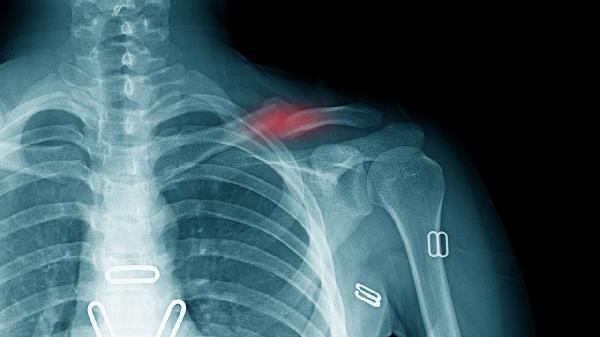

3、定期复查

术后需按医嘱定期拍摄X线片观察骨折愈合情况。首次复查通常在术后1-2周,之后每2-4周复查一次直至骨折临床愈合。若出现内固定松动、断裂或愈合延迟等情况,需及时干预处理。